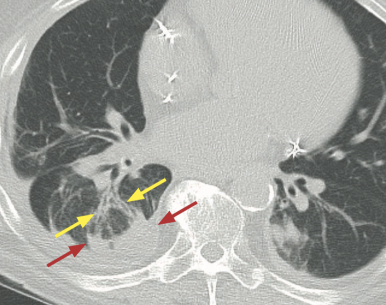

• Forme ronde

• Périphérique sous-pleurale (lobes inf post++)

• Perte de volume adjacente

• Vaisseaux et bronches courbes (“queue de comète”)

• Anomalie pleurale sous-jacente (epanchement, plaque, carcinose,…)